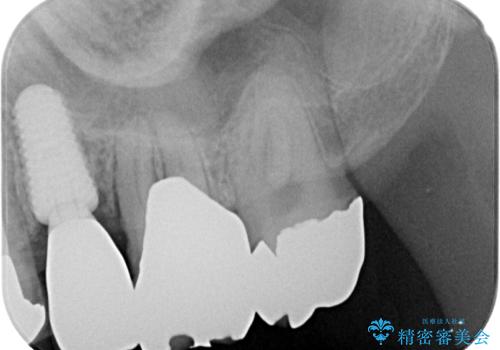

診査の結果、該当歯は**虫歯が歯肉の奥深くまで進行し、根だけが残っている状態**でした。

このようなケースでは、歯を残すことが難しく、従来なら抜歯後に一定の治癒期間をおいてからインプラント治療を行うのが一般的です。

埋入から約3か月後、最終的なセラミッククラウンを装着し、

周囲の歯と調和した自然で美しい仕上がりとなりました。